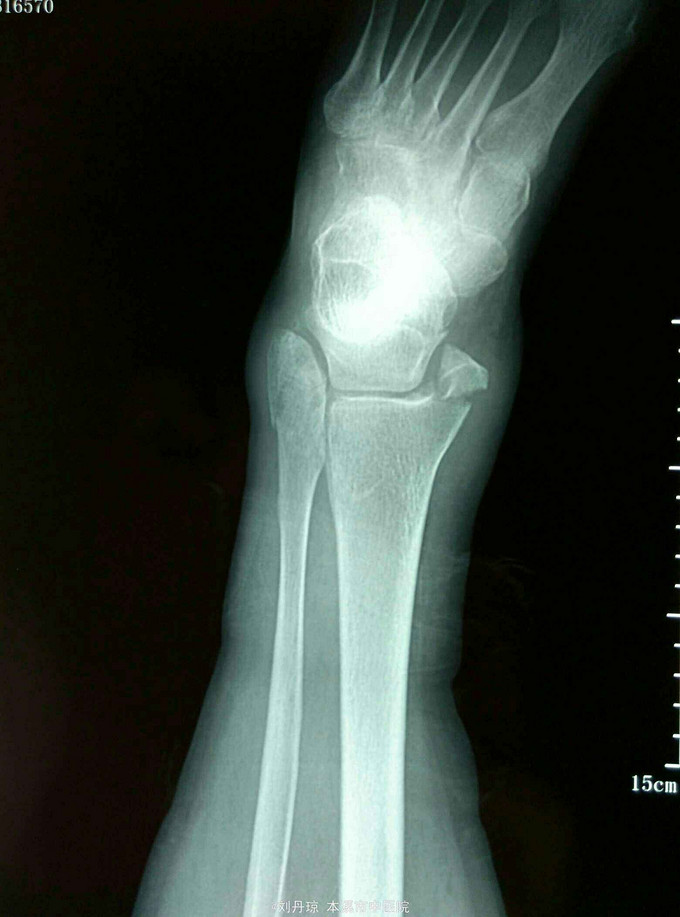

左踝关节刺痛,活动受限2小时。病史:患者2小时前下楼梯时不慎扭伤左踝,伤后左踝刺痛,活动受限,遂来我院门诊求治。既往:冠心病史20年,心梗病史1年。

左踝关节畸形,肿胀明显,压痛阳性,左踝关节功能障碍。足背动脉搏动清,足趾活动良好。辅查:DR:左踝关节骨折,三踝骨折移位明显。

诊断:左踝关节骨折 旋后外旋型IV度 治疗:手法整复,活血膏外用,夹板固定。接骨丹口服。